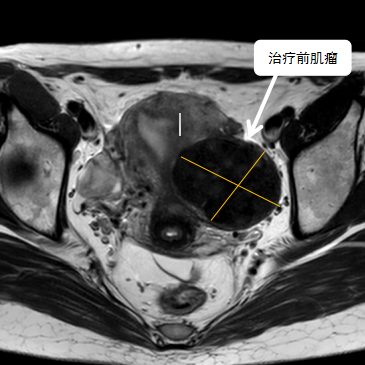

38歲的袁女士多年前發現子宮肌瘤,病情雖不嚴重,但是最近三年腫瘤在逐步增大,最大的肌瘤將近6公分,袁女士下一步面臨生育問題,如果不處理子宮肌瘤,懷孕期間激素水平的變化有可能會導致肌瘤快速增大;如果常規手術處理肌瘤,由于瘢痕粘……